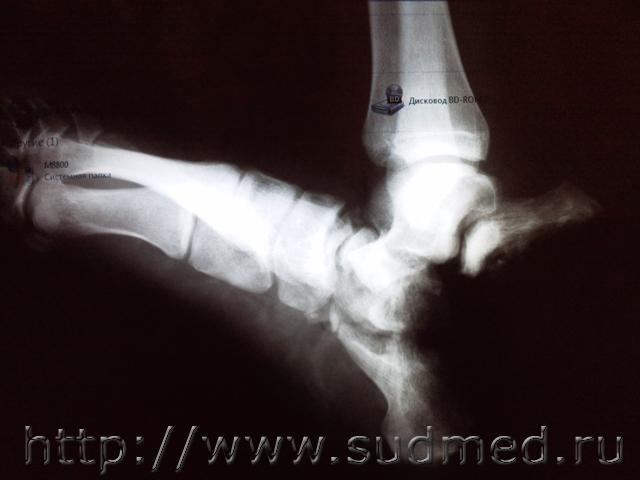

В следствии ДТП получил закрытый прелом ключицы с удовлетворительным смещением отломков, и открытый перелом пяточной кости на правой ноге с утерей фрагмента кости, а также перелом таранной кости. Было проведено 2 операции, в стационаре находился 30 дней. Какая степень тяжести нанесённого ущерба?

Эскизы прикрепленных изображений

Судебная медицина - Прикрепленное изображение Судебная медицина - Прикрепленное изображение Судебная медицина - Прикрепленное изображение